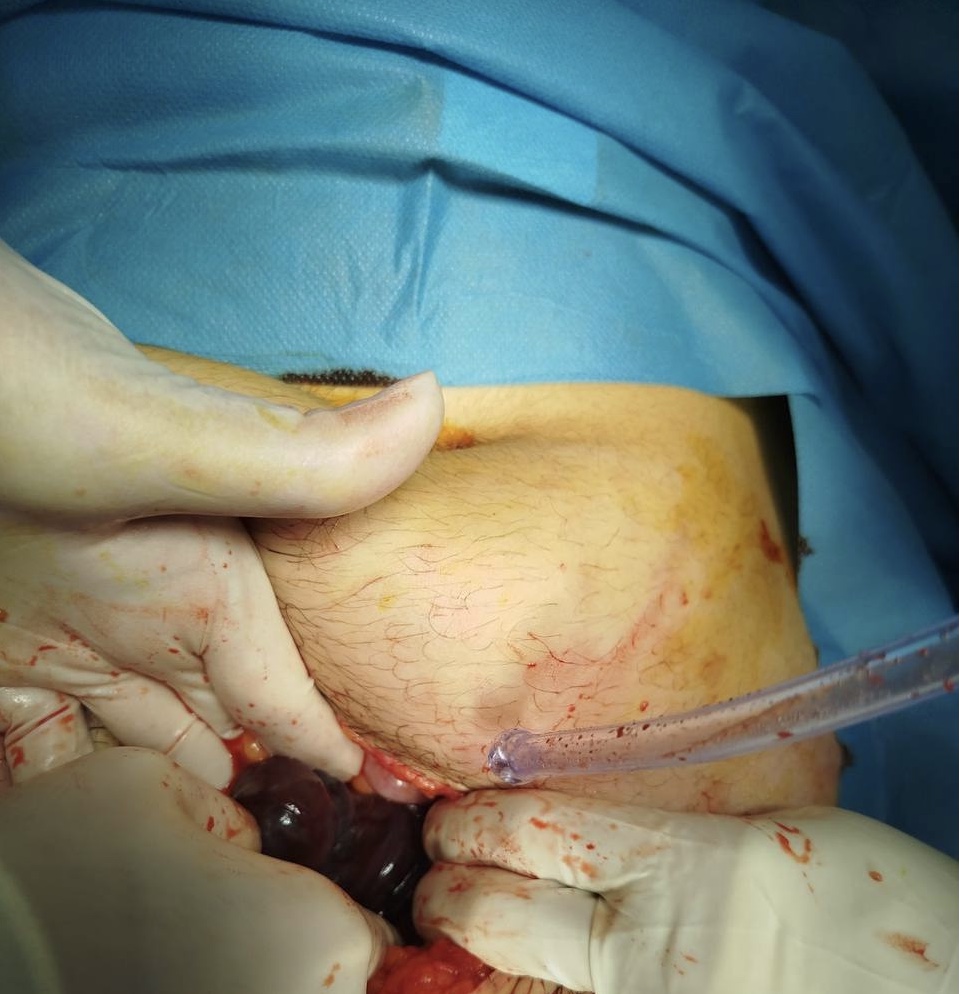

Operation :

EN